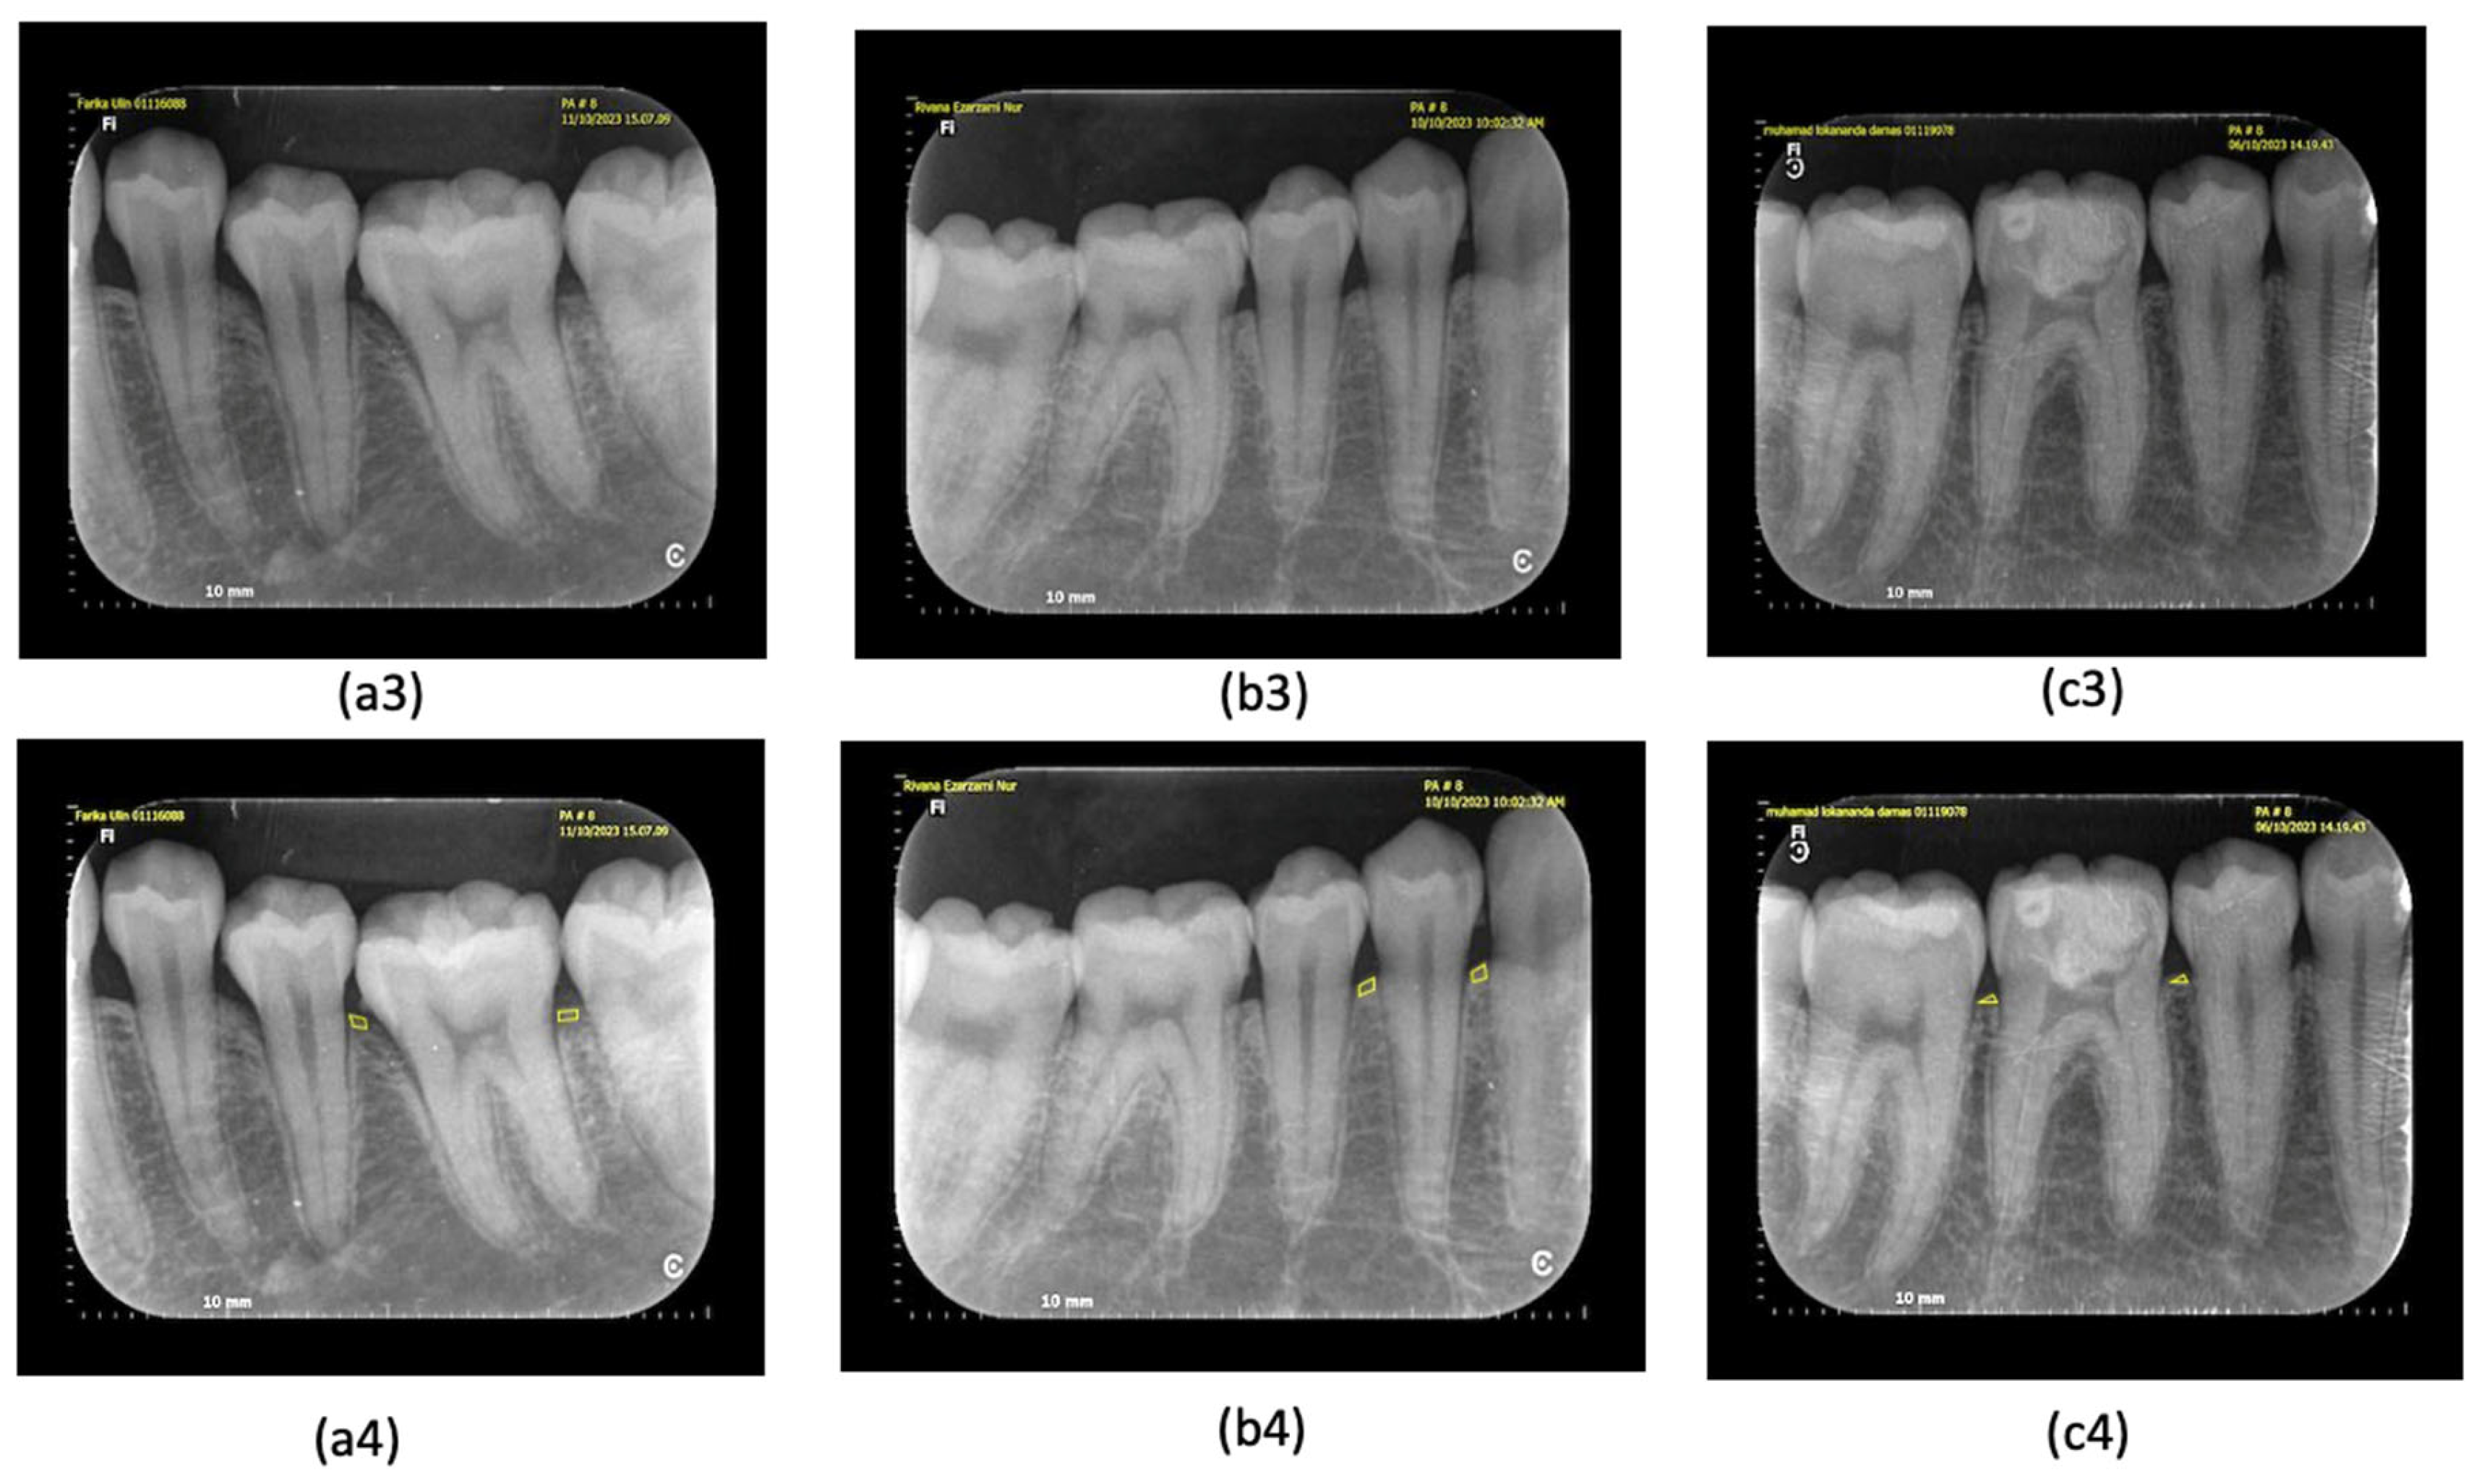

| Periapical Radiograph Examination | Irregularity of alveolar crest | 16 (40%) | 24 (60%) | 40 |

| Periodontal ligament width (PDL) | 16 (40%) | 24 (60%) | 40 |